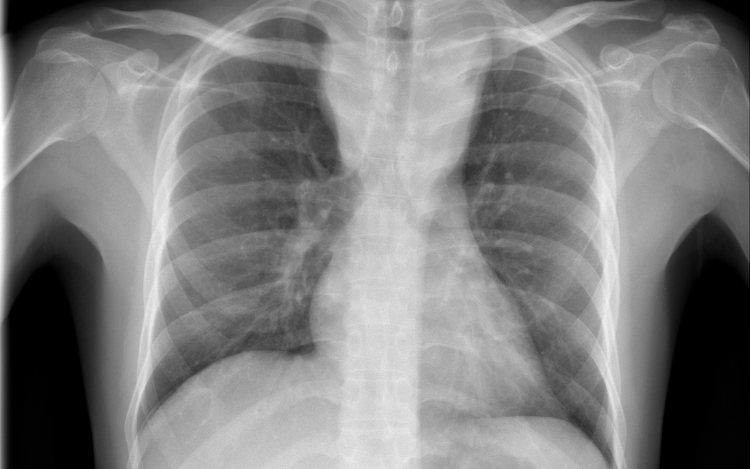

Tüdőrákban halt meg egy szervátültetett, aki egy erős dohányos tüdejét kapta meg

Tüdőrákban halt meg a transzplantáció után másfél évvel egy francia nő, akibe egy hajdan erős dohányos nő tüdejét ültették át.

A Lunc Cancer szakfolyóiratban megjelent tanulmány szerint az 57 évesen elhunyt donor 30 éven át napi egy doboz cigarettát szívott el.

A gyermekkora óta cisztás fibrózisban szenvedő páciens 2015 novemberében kapta meg a sokáig erősen dohányzó nő tüdejét, 2017 júniusában pedig bekerült a montpellier-i egyetemi klinikára, ahol két hónappal később elhunyt tüdőrákban, anélkül, hogy bármiféle terápiát alkalmazhattak volna nála. A tanulmány szerint a páciens a dohányzás okozta tüdőrák jellegzetes tüneteit mutatta.

A transzplantáció és a tüdő első rendellenességeinek röntgen általi észlelése közti rövid idő arra utal, hogy a tüdőrák már a donornál keletkezett, a szervkilökődés megakadályozására szedett immungyengítő gyógyszerek pedig csak felgyorsították a kifejlődését.

A tüdőrák hosszú lappangási idejére tekintettel a kutatók különleges elővigyázatosságot ajánlanak a dohányzó donoroktól származó szervek átültetésénél olyan esetekben, amikor a donor csak nem sokkal a transzplantáció előtt hagyott fel a dohányzással.